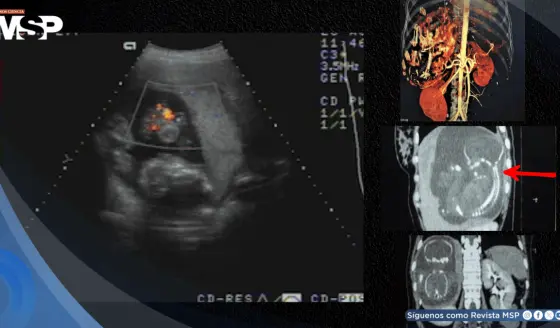

Ruptura esplénica atraumática asociada a Influenza A (H1N1) con pancreatitis en paciente de 50 años